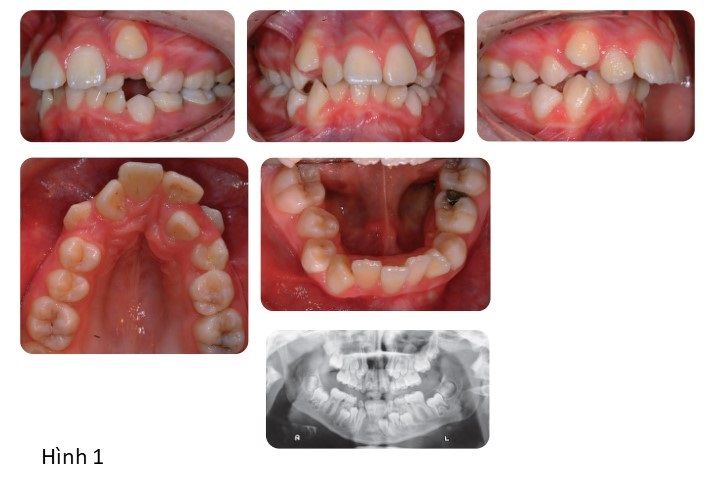

Phân tích case: Ca niềng răng thành công cho bệnh nhân bị hô, răng chen chúc, phức tạp

Bệnh nhân nữ 12 tuổi có tương quan răng cửa hạng II tiểu loại 1 trên nền xương hạng II trung bình với kích thước dọc trung bình, phức tạp bởi:

- Độ cắn chìa tăng (11 mm)

- Răng nanh bên trái hàm trên mọc lệch

- Răng hàm trên và hàm dưới mọc chen chúc nặng

- Đường giữa hàm trên bị lệch

- Răng cửa bên hàm trên bên phải mọc lệch về phía khẩu cái

- Có thể bị sâu mặt nhai răng 6 (răng hàm lớn thứ nhất) bên trái hàm trên.